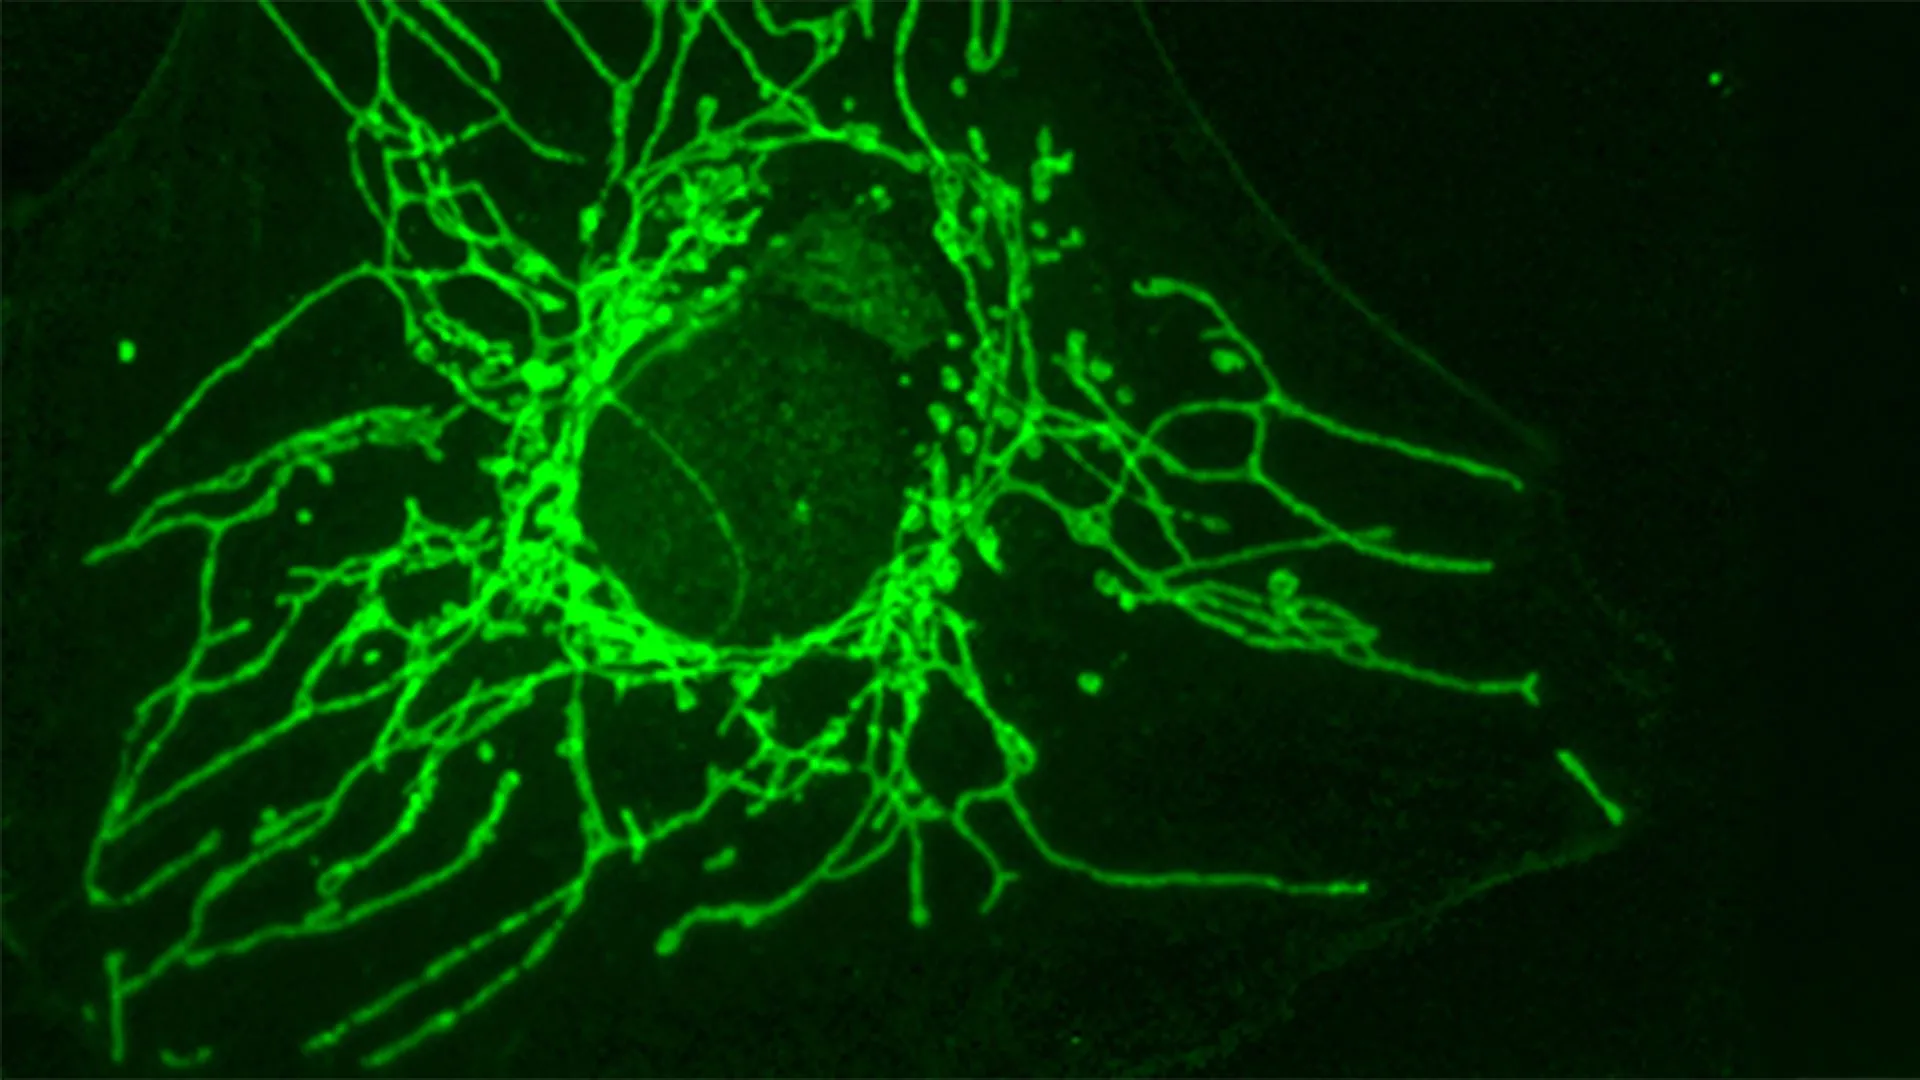

Crédito: Jornal de investigação clínica (2025). DOI: 10.1172/jci191772